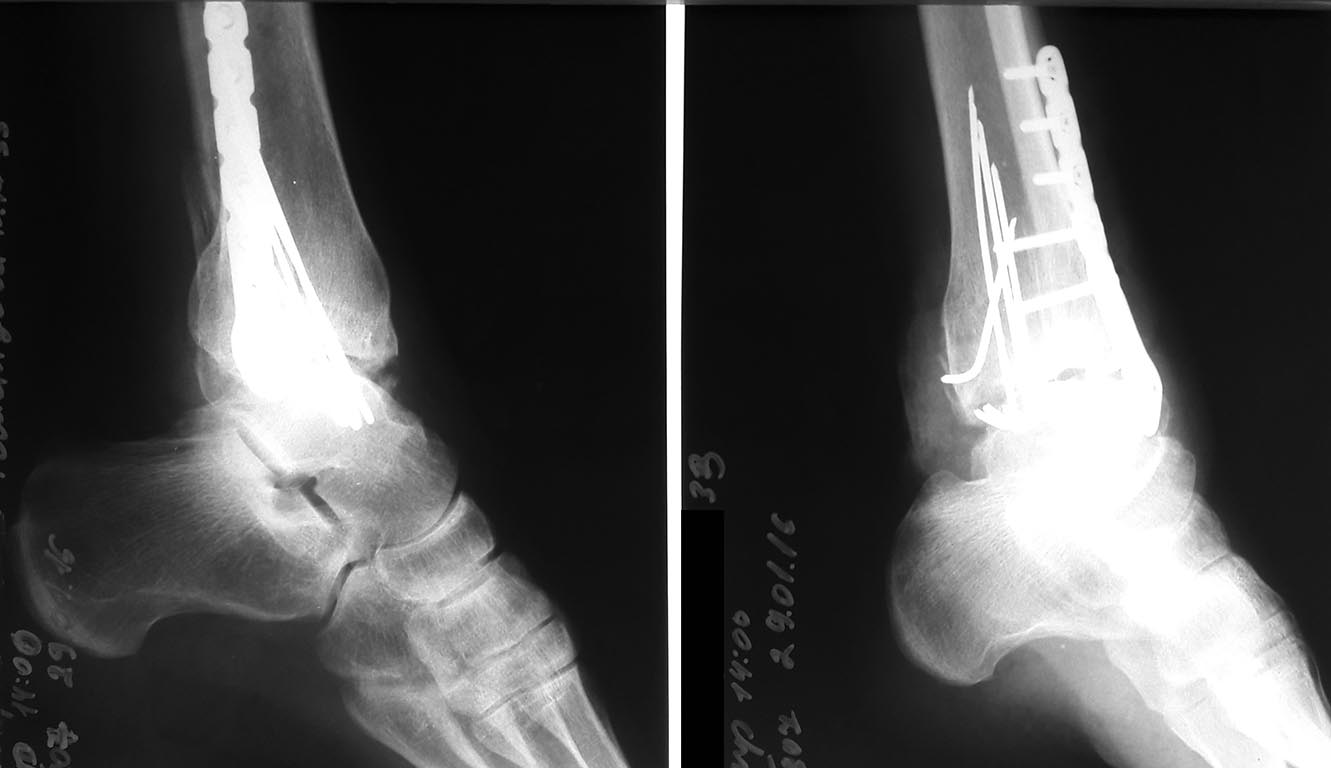

Рентгенограммы 2016